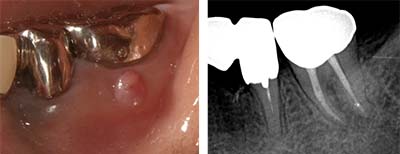

| 主訴 | 他院で2~3年前に歯根端切除した前歯が腫れて痛む |

| 所見 | #11に腫脹が認められる |

初診時(腫脹が認められる)

|

MTA根充

根充後20日(影が消える)